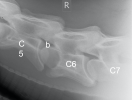

5. – 7. Halswirbel

Die Facettengelenke (a) sind schön glatt ausgebildet. Die Austrittslöcher (b) sind weit offen und geben Platz für die Halsnerven.